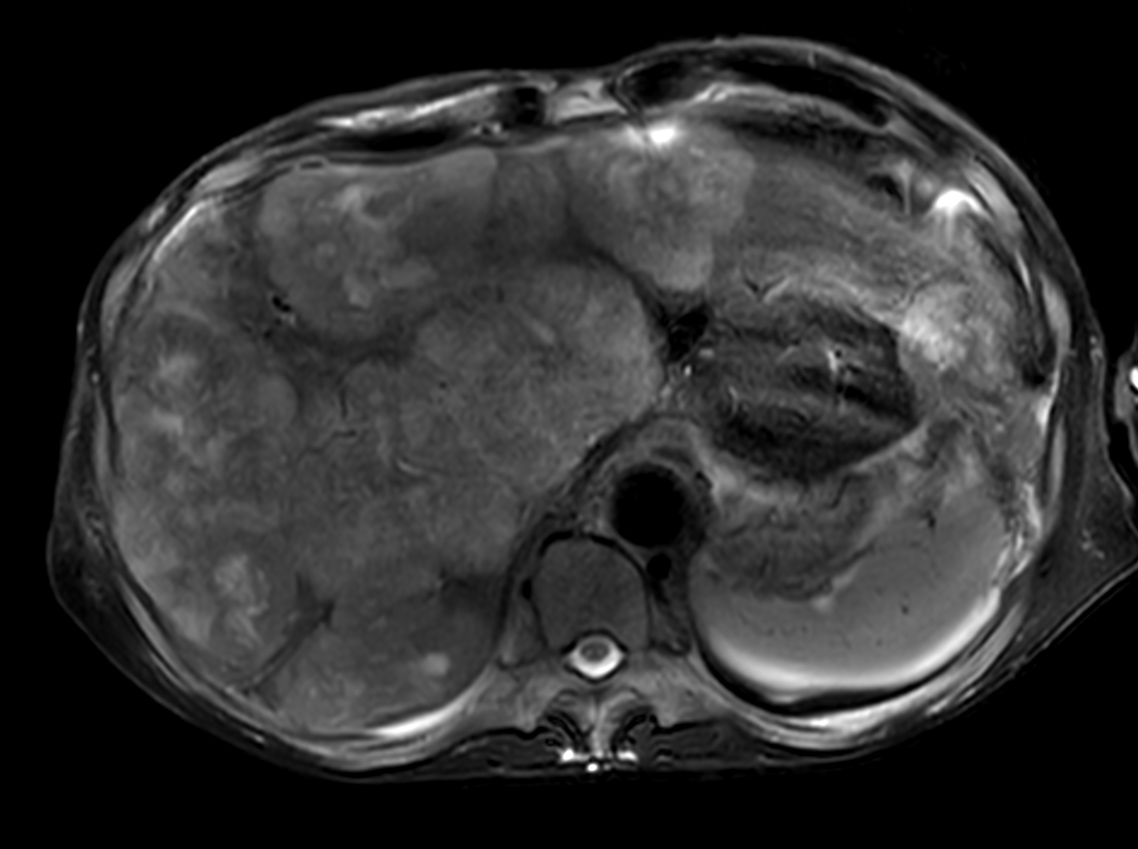

Patient with liver metastasis. The ExamCard includes techniques for efficient fat-free imaging over large field-of-views (mDIXON XD), a procedure for non-invasive liver fat quantification (mDIXON Quant), a multi-phase contrast-enhanced sequence (4D FreeBreathing) to improve imaging confidence and Compressed SENSE to accelerate the entire exam.

T2w TSE